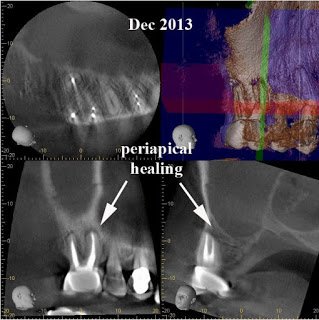

After 6 months, extraction of tooth #2 and retreatment of tooth #3 has shown periapical healing. The potential odontogenic source of the sinus infection has been eliminated. Since the Mx sinus continues to show opacification, the patient is referred back to Dr. Haegen for continued sinus evaluation and treatment.